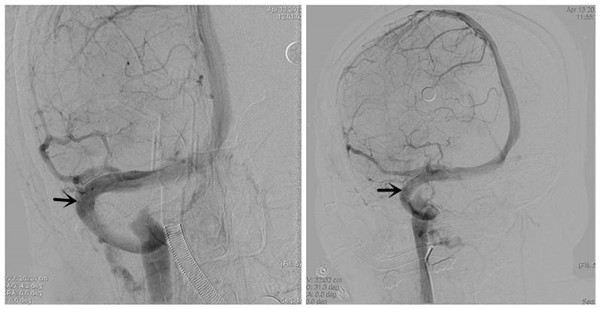

术后DSA示:右侧横窦狭窄消失